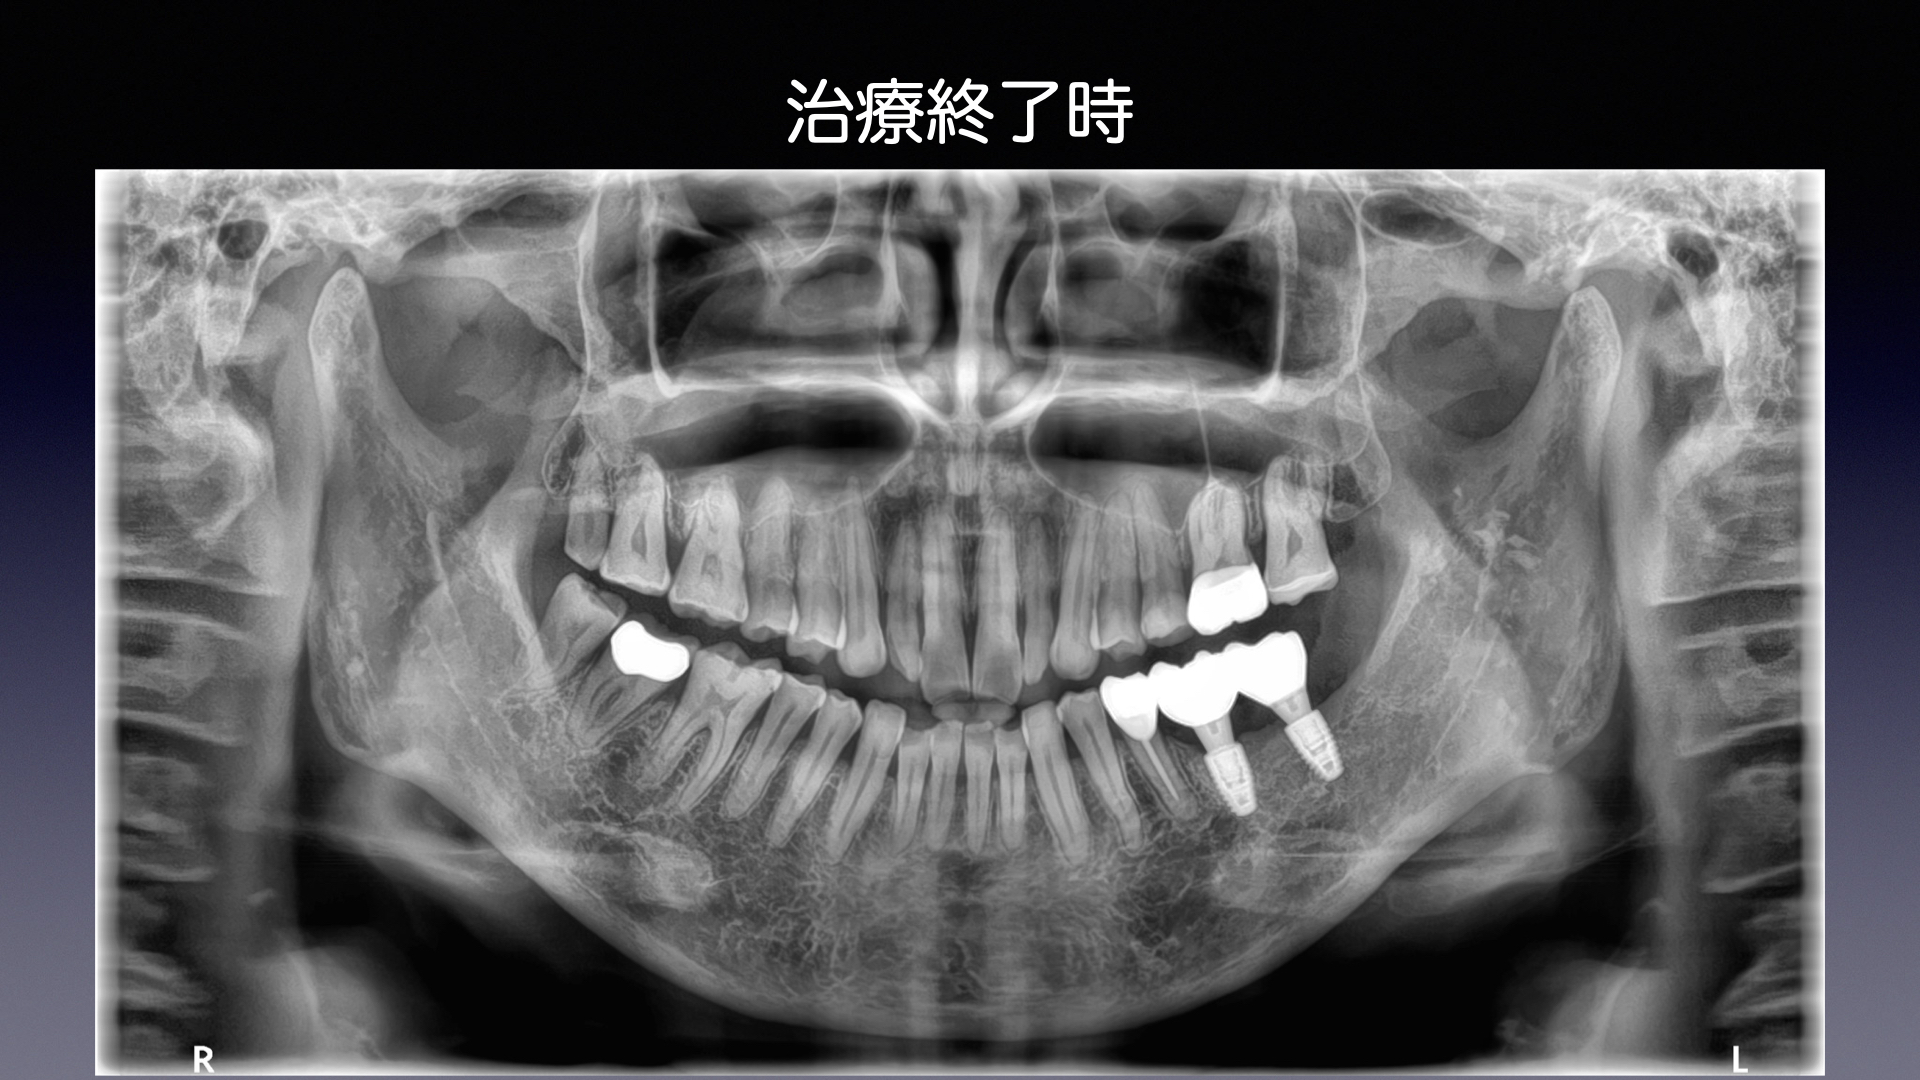

サイナスリフトと同時にインプラント埋入した症例

大臼歯を失った場合の治療法として、噛む力や食いしばる力が強い方にブリッジや入れ歯は予後が悪いといえます。 ブリッジはたわんでしまい、支えてる歯にダメージを与えます。その結果、支えている歯にトラ...